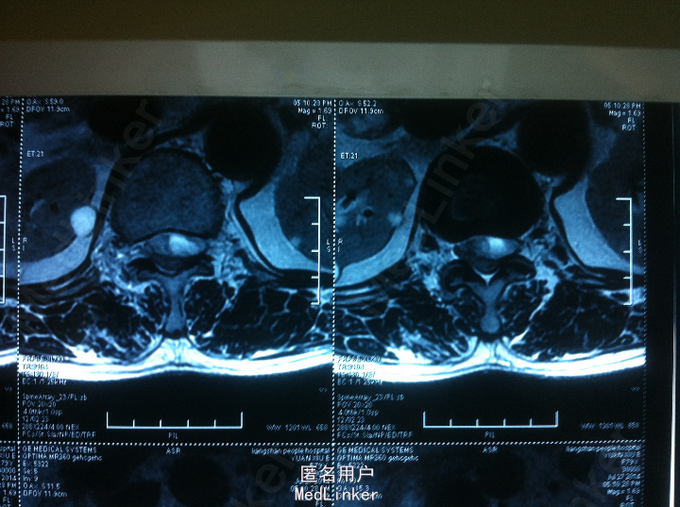

查体:腰部叩痛,双下肢感觉减退,双下肢肌力2-3级,双侧膝跟腱反射未引出,肌张力减弱,巴氏征未引出。 CT:腰椎硬膜外血肿可考虑 MR:腰椎硬膜外血肿

诊断:自发性腰椎硬膜外血肿 患者入院后给予甘露醇、甲泼尼龙、甲钴胺、神经节苷脂等药物,第二天,双下肢麻木较前减轻,双下肢肌力3-4级,与患者及家属沟通后,患者家属拒绝手术减压血肿清除,继续给予消肿、营养神经药物治疗,入院第5天,患者双下肢麻木明显消失,双下肢肌力4-5级,好转出院。